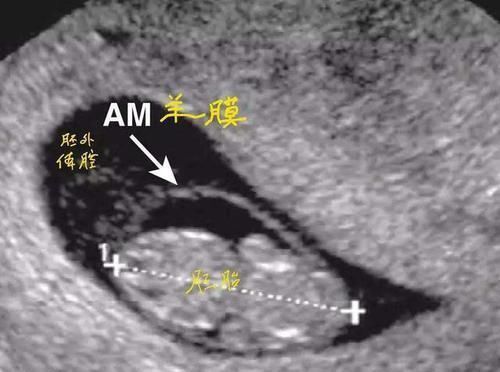

而这层保护罩其实就是羊膜,它可以起到保护小婴儿的作用。

羊膜具体有哪些作用?1、帮助宝宝呼吸

我们可以把羊膜比喻成摇篮,胎宝宝被羊膜包裹就像在摇篮中发育一样,而羊膜可以使宝宝周围的温度保持恒温,可以保证更多的氧气能帮助宝宝更好的呼吸。如果宝宝带着羊膜出生,那么便能更快地接受外界环境。